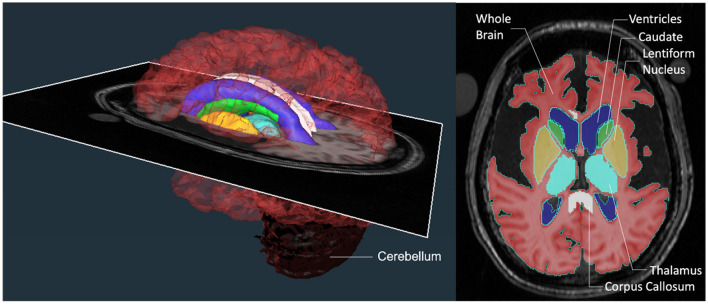

Approach: Twenty-five brain MRIs were included in this study from 22 type II GM1 patients of which 8 were late-infantile subtype and 14 were juvenile subtype. The following structures were segmented by two rating teams on a slice-by-slice basis: whole brain, ventricles, cerebellum, lentiform nucleus, thalamus, corpus callosum, and caudate nucleus. The inter- and intra-rater reliability of the segmentation method was assessed with an intraclass correlation coefficient as well as Sorensen-Dice and Jaccard coefficients.